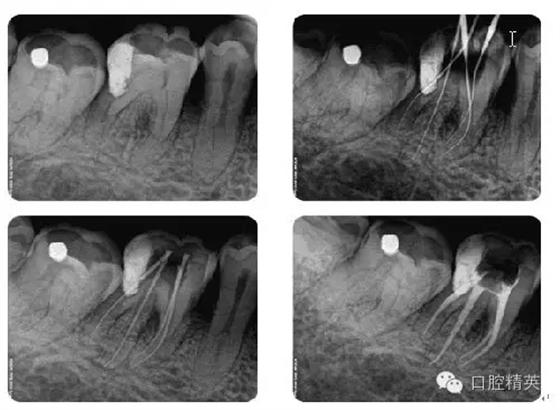

病例1:常規(guī)根管治療